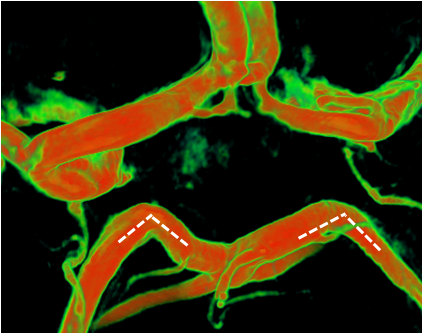

本例右侧后交通粗大(白色虚线),它的血运代偿强大到完全不需要大脑后动脉(黄色虚线)的存在,后交通直接替代了大脑后动脉,所以右侧P1纤细不显影,P2其实是后交通的延续。这种情况叫“胚胎型大脑后动脉”。这种完全型胚胎型大脑后动脉单侧出现的比列约为4-26%,双侧为2-4%    胚胎型大脑后动脉如果在起始部位发生后交通动脉瘤,那么不论手术还是介入治疗的风险都较正常的后交通动脉瘤大,一旦后交通动脉在治疗中发生损伤或闭塞,那么后果是灾难性的    本例基底动脉顶端的形态很有意思,一般情况下,基底动脉顶端分叉成两支大脑后动脉,呈“T”型。但本例因为右侧P1发育不全,基底动脉内的血流和压力直接传导到左侧P1,导致左侧P1被上抬了,基底动脉也向右侧弯曲,这种形态能更有效地传导血液和压力